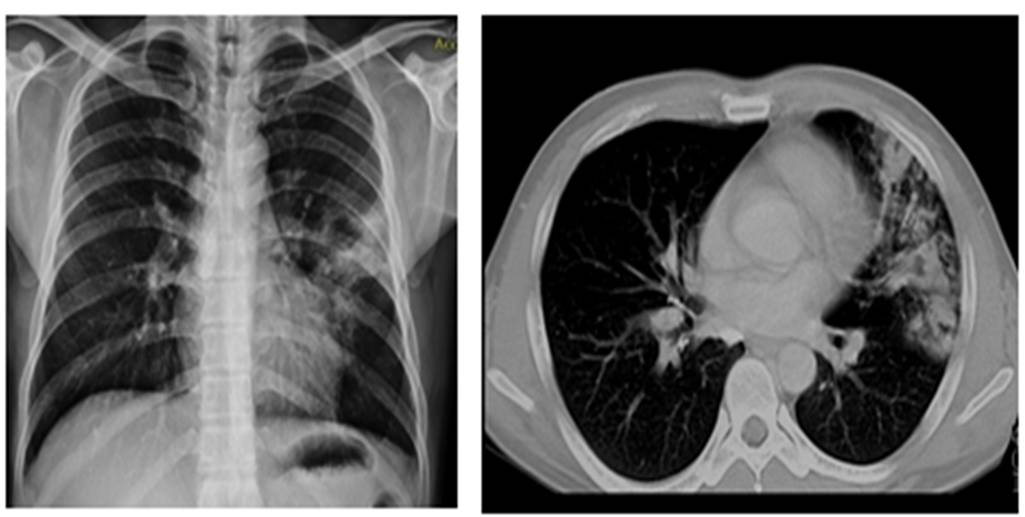

Нөгөө талаар сүрьеэ өвчин нь нэгээс нөгөөд амьсгалын замаар халдварладаг. Уушгины хэлбэрийн сүрьеэтэй өвчтэй хүнийг ярих, ханиах, найтаахад эргэн тойронд нь их хэмжээний сүрьеэгийн нян тархаж байдаг. Өвчтөнтэй ойр байсан хүмүүс уг нян агуулсан агаараар амьсгалсанаар халдвар авдаг. Шинэ эзний биед нянгийн үржих тохиромжтой хэсэг нь уушиг юм. Уушигнаас нян цусаар дамжин бусад эрхтэн системд очдог. Уушигны хэлбэрийн сүрьеэ нь халдвартай ба бусад эрхтэний сүрьеэ нь халдваргүй. Уушигны хэлбэрийн сүрьеэтэй өвчтөнтэй ойр байгаа хүмүүс халдвар авах боломж их байдаг. Сүрьеэгийн нянгийн халдвар авсан хүн болгон сүрьеэгээр өвчлөхгүй. Энэ нь хүний дархлалын систем буюу биеийн эсэргүүцэлтэй ихээхэн холбоотой. Хүмүүсийн дархлал нь өвчин үүсгэгч нянгийн идэвхжлийг зогсоон удаан хугацаагаар хяналтандаа барьж байдаг. Гэвч ямар нэг хүчин зүйлийн нөлөөгөөр дархлалын систем нь суларвал "зүүрмэглэж байсан" сүрьеэгийн нян идэвхтэй үржиж өвчнийг үүсгэдэг гэмтэй. Тиймээс сүрьеэ дагасан асуудал их. Ямартай ч XXI зууны монголын эмгэнэл болсон эл асуудлыг дагасан олон хэрэг дардайх бололтой.